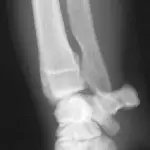

Figure 3A. This series represents an example of a probable fracture that cannot be seen on routine radiographs but that produces secondary signs that can be seen. Slight thickening of the caudal cortex of the tibia (arrow) is present in a dog with left hind limb lameness. The dog is an active, 3-yearold, castrated male black Labrador retriever having lameness for several months but with no prior history of lameness.

Figure 3B. Lameness was persistent, and cortical thickness progressed (arrow) over a 4-month period. Panosteitis might be considered in the differential diagnosis because of the several areas of uptake, although panosteitis does not typically start as a focal unicortical thickening of the bone in a 3-year-old dog.

Figure 3C. A bone scan was positive in the shaft of the tibia and was suggestive of a hairline stress fracture.

Figure 3D. Several small holes were drilled in the affected cortex (osteostixis) to encourage neovascularization and bone healing. The lameness resolved after treatment.